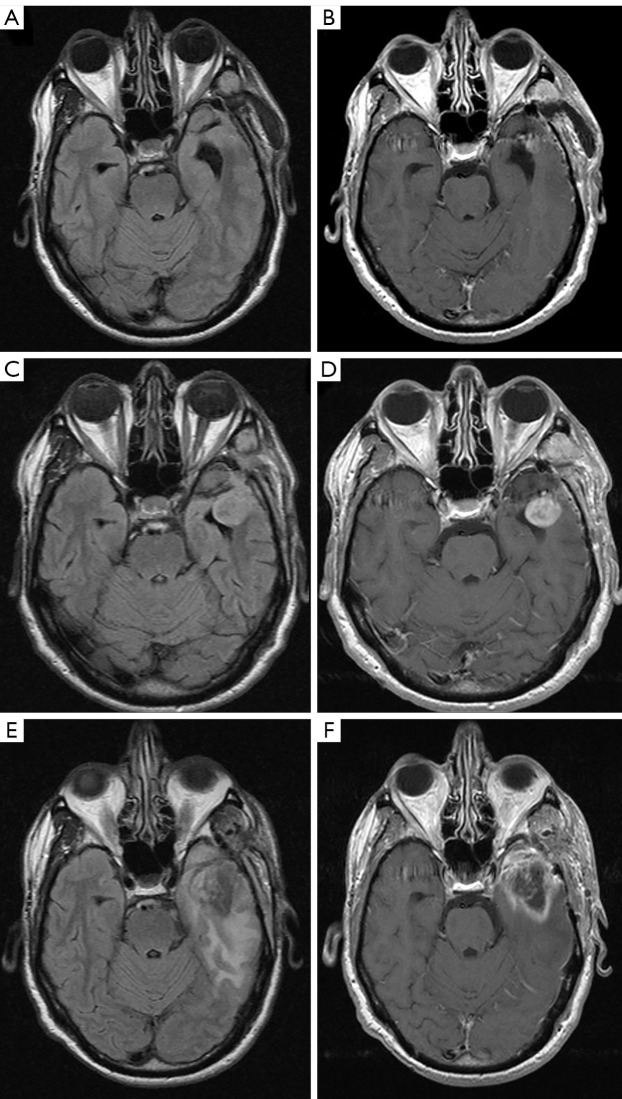

背景:2018年提出了一种新的成人脑肿瘤治疗后磁共振成像分类和报告系统,命名为脑肿瘤报告和数据系统(BT-RADS),需要通过协议研究的方式进行验证。方法:采用回顾性研究方法,对在法国国立政治医学基金会(Fondazione Policlinico Campus Bio-Medico)进行随访的原发性脑肿瘤成年患者进行磁共振成像(MRI)检查。4名放射科医生(2名住院放射科医生,1名普通放射科医生,1名神经放射科医生)阅读并使用BT-RADS评分工具对每项研究进行评分,对MRI原始报告不知情。计算观察者间一致性和Fleiss’k来评估诊断一致性的水平。评估了多少次分配不同的BT-RADS评分会导致不同的患者管理。结果:纳入研究的患者总数为23例,mri 147例,回顾性评估BT-RADS评分588分。两种最常见的肿瘤类型是星形细胞瘤4级(62%)和少突胶质细胞瘤3级(21%)。所有4位放射科医生的总体一致性率为82%,Fleiss’k为0.70。普通放射科医生和神经放射科医生的总体一致性为91%,Fleiss’k为0.86。2名放射科住院医师与神经放射科医师的总体一致性率为80%,Fleiss’k为0.66。星形细胞瘤3级(k: 0.51)和少突胶质细胞瘤2级(k: 0.32)的一致性较差,而星形细胞瘤4级(k: 0.70)、星形细胞瘤2级(k: 0.78)和少突胶质细胞瘤3级(k: 0.78)的一致性较高。所有放射科医生同意70%患者的BT-RADS分配,三位放射科医生同意17%,两位放射科医生同意13%。在任何情况下,读者之间都没有完全的分歧。在18%的病例中,估计的BT-RADS的差异会导致不同的后续管理。结论:对于神经放射科医生和放射科医生来说,BT-RADS可以被认为是一种有效的工具,即使他们在成人原发性脑肿瘤随访期间对患者图像的解释经验很少,也可以支持标准化的解释、报告和临床管理。

Methods: A retrospective study was designed with the aim of identifying contrast-enhanced magnetic resonance imaging (MRI) of adult patients on follow-up for primary brain tumor at Fondazione Policlinico Campus Bio-Medico. Four radiologists (2 radiology residents, 1 general radiologist, 1 neuroradiologist) read and scored each study using the BT-RADS scoring tool, blinded to the MRI original report. Interobserver agreement and Fleiss' k were calculated to assess the level of diagnostic agreement. It was assessed how many times the assignment of different scoring of BT-RADS would have led to a different patient management.

Results: The total number of patients included in the study was 23 with 147 MRIs and a total of 588 BT-RADS scores retrospectively evaluated. The two most frequent tumor types were astrocytoma grade 4 (62%) and oligodendroglioma grade 3 (21%). The overall agreement rate for all 4 radiologists was 82% with a Fleiss' k of 0.70. The overall agreement rate between general radiologist and neuroradiologist was 91% with a Fleiss' k of 0.86. The overall agreement rate between 2 radiology residents and neuroradiologist was 80% with a Fleiss' k of 0.66. Astrocytoma grade 3 (k: 0.51) and oligodendroglioma grade 2 (k: 0.32) showed a poor agreement while higher values of agreement were found for astrocytoma grade 4 (k: 0.70), astrocytoma grade 2 (k: 0.78) and oligodendroglioma grade 3 (k: 0.78). All the radiologists agreed on BT-RADS assignment in 70% patients, three radiologists agreed in 17% and two radiologists agree in 13%. In no cases there was a complete disagreement among the readers. In 18% of cases the discrepancy in the estimated BT-RADS would have led to a different follow-up management.